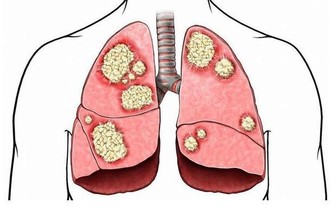

危害嚴重的眼底出血

眼底出血是指眼內視網膜出血,或玻璃體內積血。此現像只靠肉眼是看不到的,早期也可無明顯表現,需通過專業的眼底檢查才能發現異樣,相比眼表出血危險性也更大。

眼底出血症狀

眼底出血會出現視力下降、視野缺損,或是眼前有黑影、看東西變形等情況。

因此,醫生提示,平時一旦視物“異常”,則應立即到醫院進行眼壓、眼底照相、眼底熒光血管造影等檢測,切勿任其不管,以免造成嚴重後果。

眼底出血原因

眼底出血不是一種獨立的眼病,而是許多眼病和某些全身性疾病所共有的特性。以下四類人群尤其要注意眼底出血狀況: